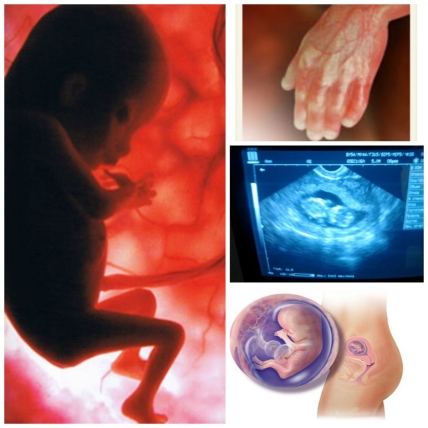

БУДУЩИЙ МАЛЫШ НА 12 НЕДЕЛЕ БЕРЕМЕННОСТИ

12 неделя беременности: ваш малыш уже длиной около 6-7 см. и весит 9-13 грамм, его сердечко бьется 110-160 ударов в минуту, в крови появились лейкоциты, гипофиз уже производит гормоны, влияющие на рост и обмен веществ маленького организма, а за развитие иммунитета отвечает вилочковая железа, сформировавшаяся к этому времени.

Ребенок умеет переворачиваться, отталкиваться, зажмуриваться, открывать рот, шевелить пальцами, сосать свой большой палец и заглатывать околоплодную жидкость, которая потом выходит из его организма в виде мочи.

Все более зрелыми становятся внутренние системы его организма: печень начала вырабатывать желчь, тонкий кишечник освоил перистальтику, оформились половые органы.

На пальчиках малыша уже видны маленькие ноготки, на теле – первые волоски, в хрящевом скелете начался процесс образования костного вещества.